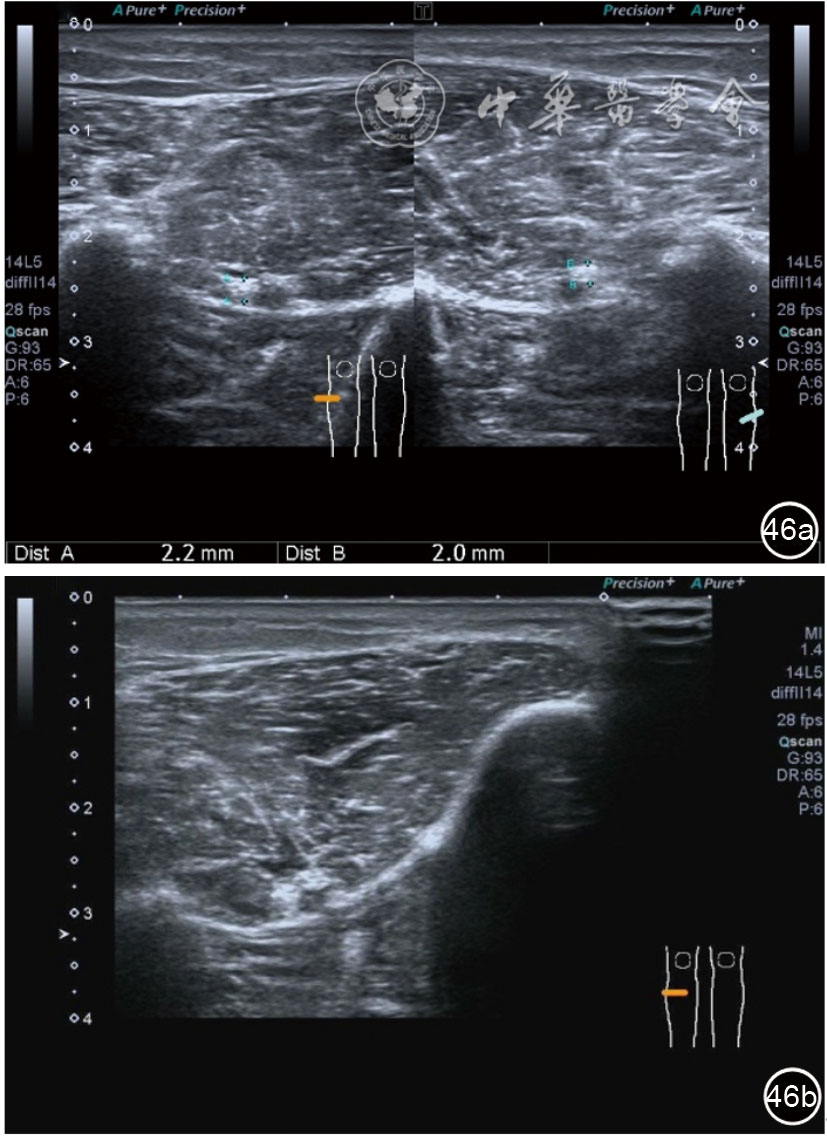

2.腓总神经卡压静态结构针刀切割松解治疗。体位与治疗前准备同局部液压松解加药物注射治疗。治疗点在卡压最明显的部位,一般有两个部位,一是入腓骨长肌前,腘肌与股二头肌筋膜构成的纤维通道;二是腓总神经进入腓骨长肌内的腓骨长肌筋膜。(1)入腓骨长肌前腓管针刀切割松解治疗。找到腓总神经卡压最明显处,应用25G注射针头抽吸0.5%利多卡因6~8 ml,从近端穿刺,沿腓总神经长轴在筋膜与神经之间注射,分离扩张腓管,满意后用直径1.0 mm的Ⅰ型2号针刀由近端向远端平面内进刀,由浅入深切割分离的腓管筋膜,直至松解彻底拔出针刀(图40),局部压迫止血5分钟,无菌敷料覆盖。(2)入腓骨长肌腓管针刀切割松解治疗。长轴找到腓总神经卡压最明显处,将探头转为短轴,应用25G注射针头抽吸0.5%利多卡因6~8 ml,于腓管筋膜表面和筋膜与神经之间注射,分离扩张腓管,满意后用直径1.0 mm的Ⅰ型2号针刀由后向前平面内进刀,由浅入深切割分离的腓管筋膜,直至松解彻底拔出针刀(图41),局部压迫止血5分钟,无菌敷料覆盖。

图41 超声引导下入腓骨长肌腓管针刀切割松解治疗